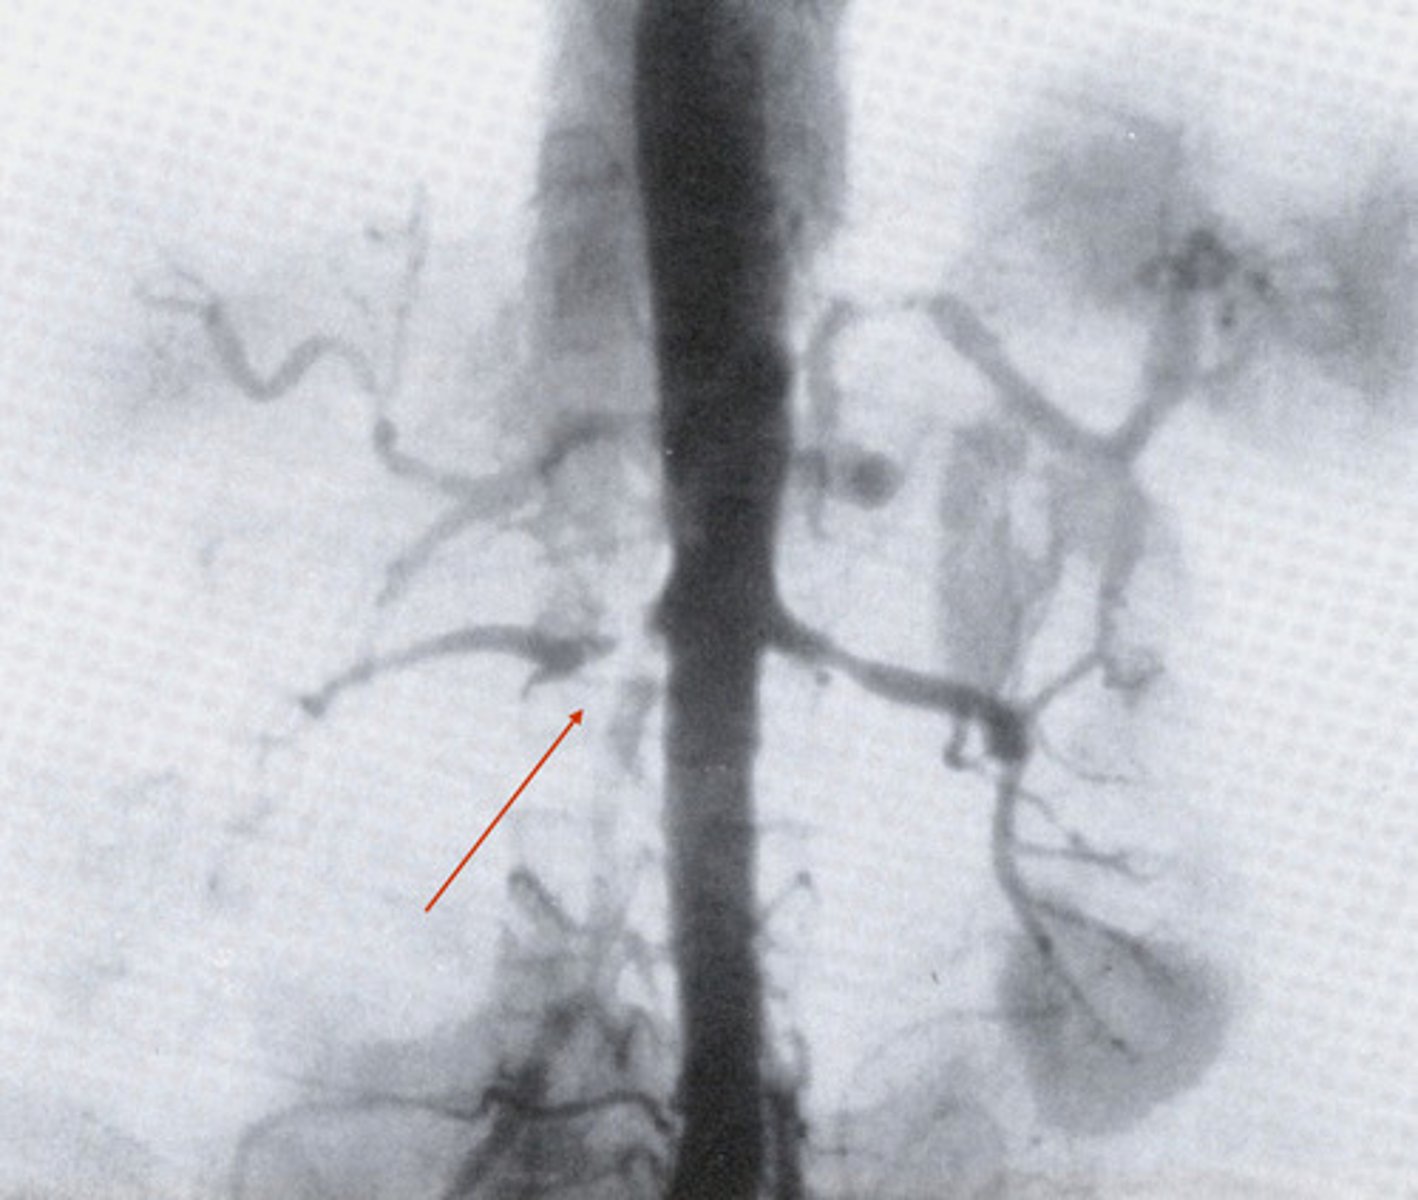

Renal Hypertension

What can be caused by stenosis (narrowing) in the renal arteries?